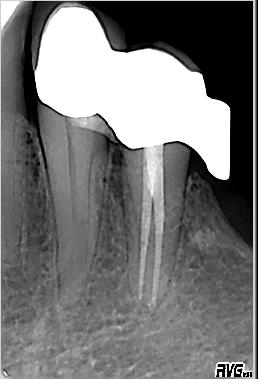

Röntgenologischer Ausgangsbefund im Januar 1993 bei Zahn 34 unmittelbar vor ZE Neuversorgung. Als sicheres Zeichen für das Vorhandensein zweier Kanalsysteme ist das scheinbar abrupte Verschwinden des im koronalen Wurzeldrittels deutlich sichtbaren „Pulpastumpfes“ zu werten